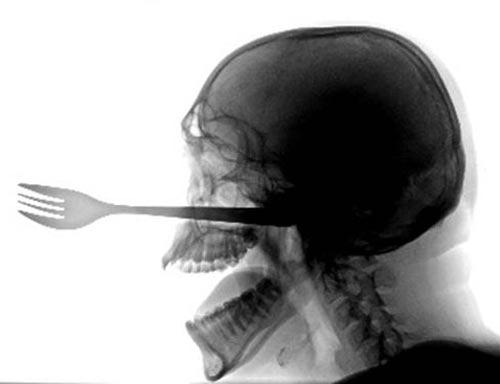

Некоторые обращались за хирургической помощью. Причём их травмы были вызваны какими-то уж чересчур изощрёнными манипуляциями. Так, один глотатель серьёзно порезал глотку, пытаясь проглотить сильно изогнутую саблю. А другой травмировал пищевод – попугай, сидевший во время представления у шпагоглотателя на плече, вдруг начал как-то дурно себя вести, чем и предрёк трагический исход шоу.

Ещё одна серьёзная травма случилась из-за того, что во время представления зритель попытался засунуть деньги за пояс трюкачке, которая с тремя проглоченными саблями исполняла танец живота ! Много ли было денег – не сообщается. Но известно, что в итоге лезвия неким образом сработали как ножницы, результатом чего стало сильное кровотечение…